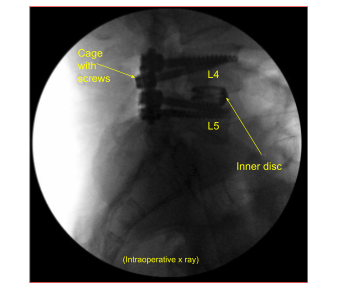

The patient was taken to the operating room where general anesthesia was induced. Neuromonitoring was established. Foley catheter was passed. The patient was turned to a prone position on a four post Jackson table.

The incision was created along the same previous incision. The incision was extended proximally. Deep dissection was done along the line of incision. The spinous process of L3 and L5 were exposed to find normal territory. The dissection was carried out deep and laterally on to the screws.

The set screw from left L4 was found to be dislodged into the soft tissue. It was removed. Further dissection was done on the transverse process of the L4 on the right side There was soft callus present. The decortication of L4 and L5 transverse processes and the pars was performed with intent to achieve fusion in the region.

A small BMP was opened in preparation for the fusion. Revision decompression of the L4-5 was performed with inferior laminectomy of the L3. The bone was used for local autograft. A thorough decompression of the L4 and L5 of the left and right was performed with the use of curettes followed by Kerrison punch. Full decompression could be achieved. A new set screw was put on to the left L4 and torqued in the usual fashion.